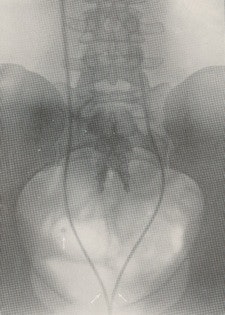

Following the discovery of the x-ray in 1895, Hurry Fenwick was an enthusiastic supporter of the new technique.2 A radiopaque ureteric bougie was passed and a radiograph was made. The position of an opacity in relation to the ureter could be determined with confidence and a phlebolith distinguished from a ureteric calculus (figure 1).

He commented on the distressing situation with the failure of operative surgery when a kidney was opened and damaged to remove a stone when it was no longer in the kidney and was now in the ureter. He estimated that this happened in about 30% of cases when the "x-ray expert" was not called upon to help in the diagnosis. The "x-ray expert" (radiologist) can "guide the urinary surgeon [urologist] with a precision unattainable before the introduction of the [x-ray] method is without cavil."